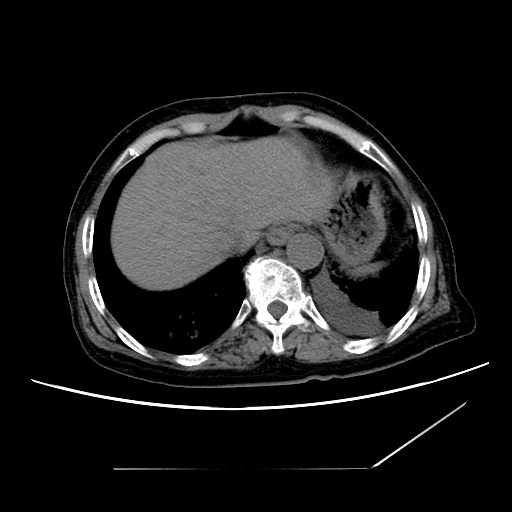

标题: CT25393:病人45岁,咳嗽,吐黄痰带血丝,发热,胸闷月余 [打印本页]

标题: CT25393:病人45岁,咳嗽,吐黄痰带血丝,发热,胸闷月余

1、左肺中央型肺癌并双肺弥漫性转移   2、双肺部感染    3、肺大泡     4、左侧胸腔积液

双侧肺弥漫性病变,可见“空泡征”及“蜂窝征”,考虑肺泡癌可能性大,左侧胸腔积液,考虑胸膜受累可能!

1)不排除肺泡癌可能。2)左侧胸腔积液。